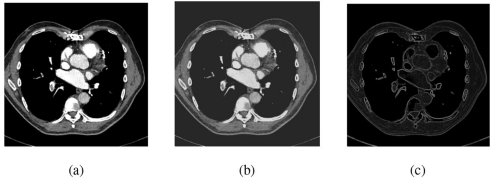

Abeer Abdelhamid团队在《Scientific Reports》发表的这项研究,开创性地将CNN的局部特征提取优势与Transformer的全局建模能力相结合。研究团队采用RSNA-STR公开数据集(包含12,000例CTPA扫描),通过患者级别的70:15:15划分确保数据独立性。关键技术包括:1)自编码器(AE)构建的预处理管道,将图像压缩至128维潜在空间;2)离散小波变换(DWT)四子带分解增强多尺度特征;3)Sobel算子边缘检测强化血栓边界;4)集成ResNet50、DenseNet121和Swin Transformer的堆叠模型,通过逻辑回归元学习器融合预测结果。

【数据预处理】研究团队设计的混合预处理管道展现出强大效能。自编码器将512×512 DICOM图像压缩至224×224×3尺寸,同时保留关键空间特征。DWT分解产生的LL、LH、HL、HH四个子带中,采用贝叶斯收缩阈值法滤除噪声,